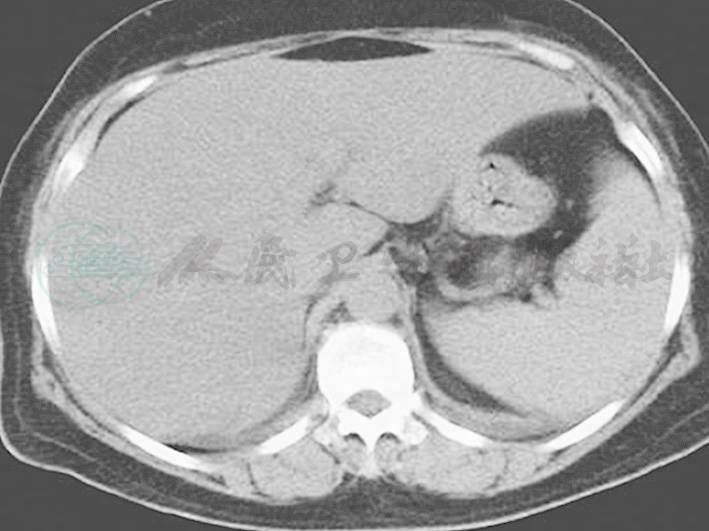

图2 胸腹部CT

脾肿大(7月8日)